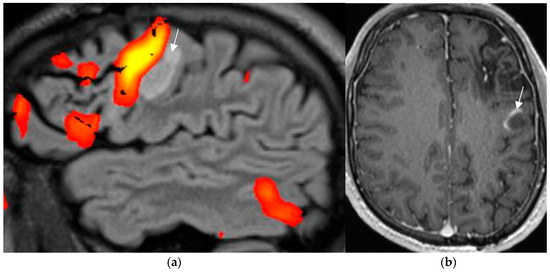

The SWI sequence depicts hemosiderin and calcification and thus renders visible cavernoma and cerebral and superficial siderosis as figureheads of cerebral amyloid angiopathy or posttraumatic or postsurgical siderosis (Figure 4).

Figure 4.

Amyloid angiopathy as evidenced by superficial siderosis within the right central sulcus on SWI sequence (arrow in (a)); invisible on the corresponding axial T2 w image (b); patient with focal seizures localized within the left hand.

Based on the SWI sequence, additional information was obtained in 13/59 (22%) of patients assessed by 1.5T MR [73].

A less-recognized feature of the SWI sequence is the paramagnetic effect of deoxyhemoglobin as a surrogate marker of vessel caliber. Pseudonarrowing of vessels may serve as a sign of regional hyperperfusion (Figure 5) and, thus, may indicate nonconvulsive status epilepticus [74,75].

Figure 5.

Non-convulsive absence status with left-sided pseudonarrowing of the mesiotemporal portion of basal vein (arrow in (a)) and hippocampal veins (arrowhead in (a)) as compared to the normal right side and mesiotemporal hyperperfusion; (CBF = cerebral blood flow image (b)) indicated by left light-green mesiotemporal hypervascularity (arrow in (b)).